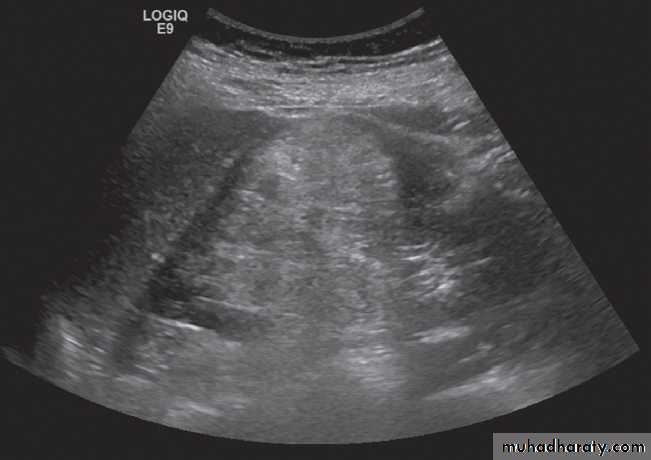

Ultrasound is the initial imaging investigation in most suspected renal abscesses, although in patients who are very unwell CT is often the first imaging investigation.Intrarenal abscesses may have thick walls and show both cystic and solid components recognizable at both ultrasound and CT, but may just look like a simple cyst.

Perinephric abscesses :may conform to the shape of the underlying kidney. The CT and sonographic characteristics are variable, usually showing both solid and cystic elements .